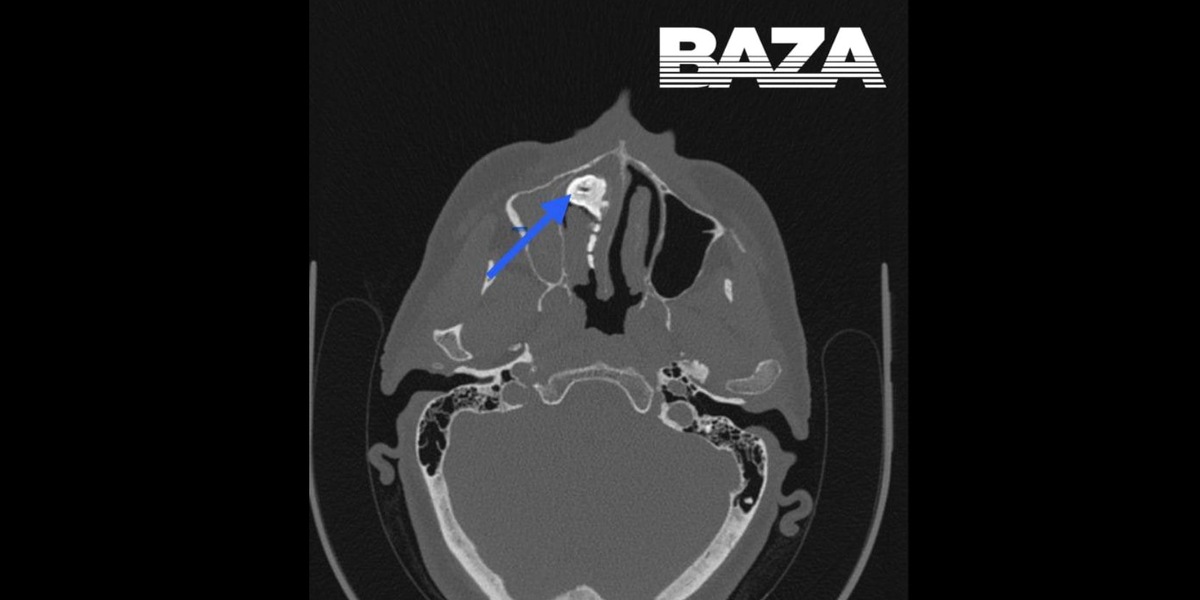

В Московской области врачи обнаружили в голове у женщины орех размером с перепелиное яйцо. Об этом сообщает Telegram-канал Baza.

Женщина обратилась к врачам, потому что ей стало тяжело дышать, она чувствовала неприятный запах, боль в носу и странные выделения. Врачи сделали рентген и обнаружили в голове женщины крупный предмет. Объяснить, что это может быть, пациентка не смогла. Однако вспомнила, что несколько лет назад вдохнула что-то мелкое, но дискомфорта после этого не испытывала, поэтому за помощью не обратилась. Неприятные симптомы появились только несколько месяцев назад.

Женщине провели операцию под местной анестезией. Крупный предмет извлекали несколькими частями. Это оказался орех, покрытый слизью полости носа. После операции все симптомы сразу же прошли. Женщину уже выписали.